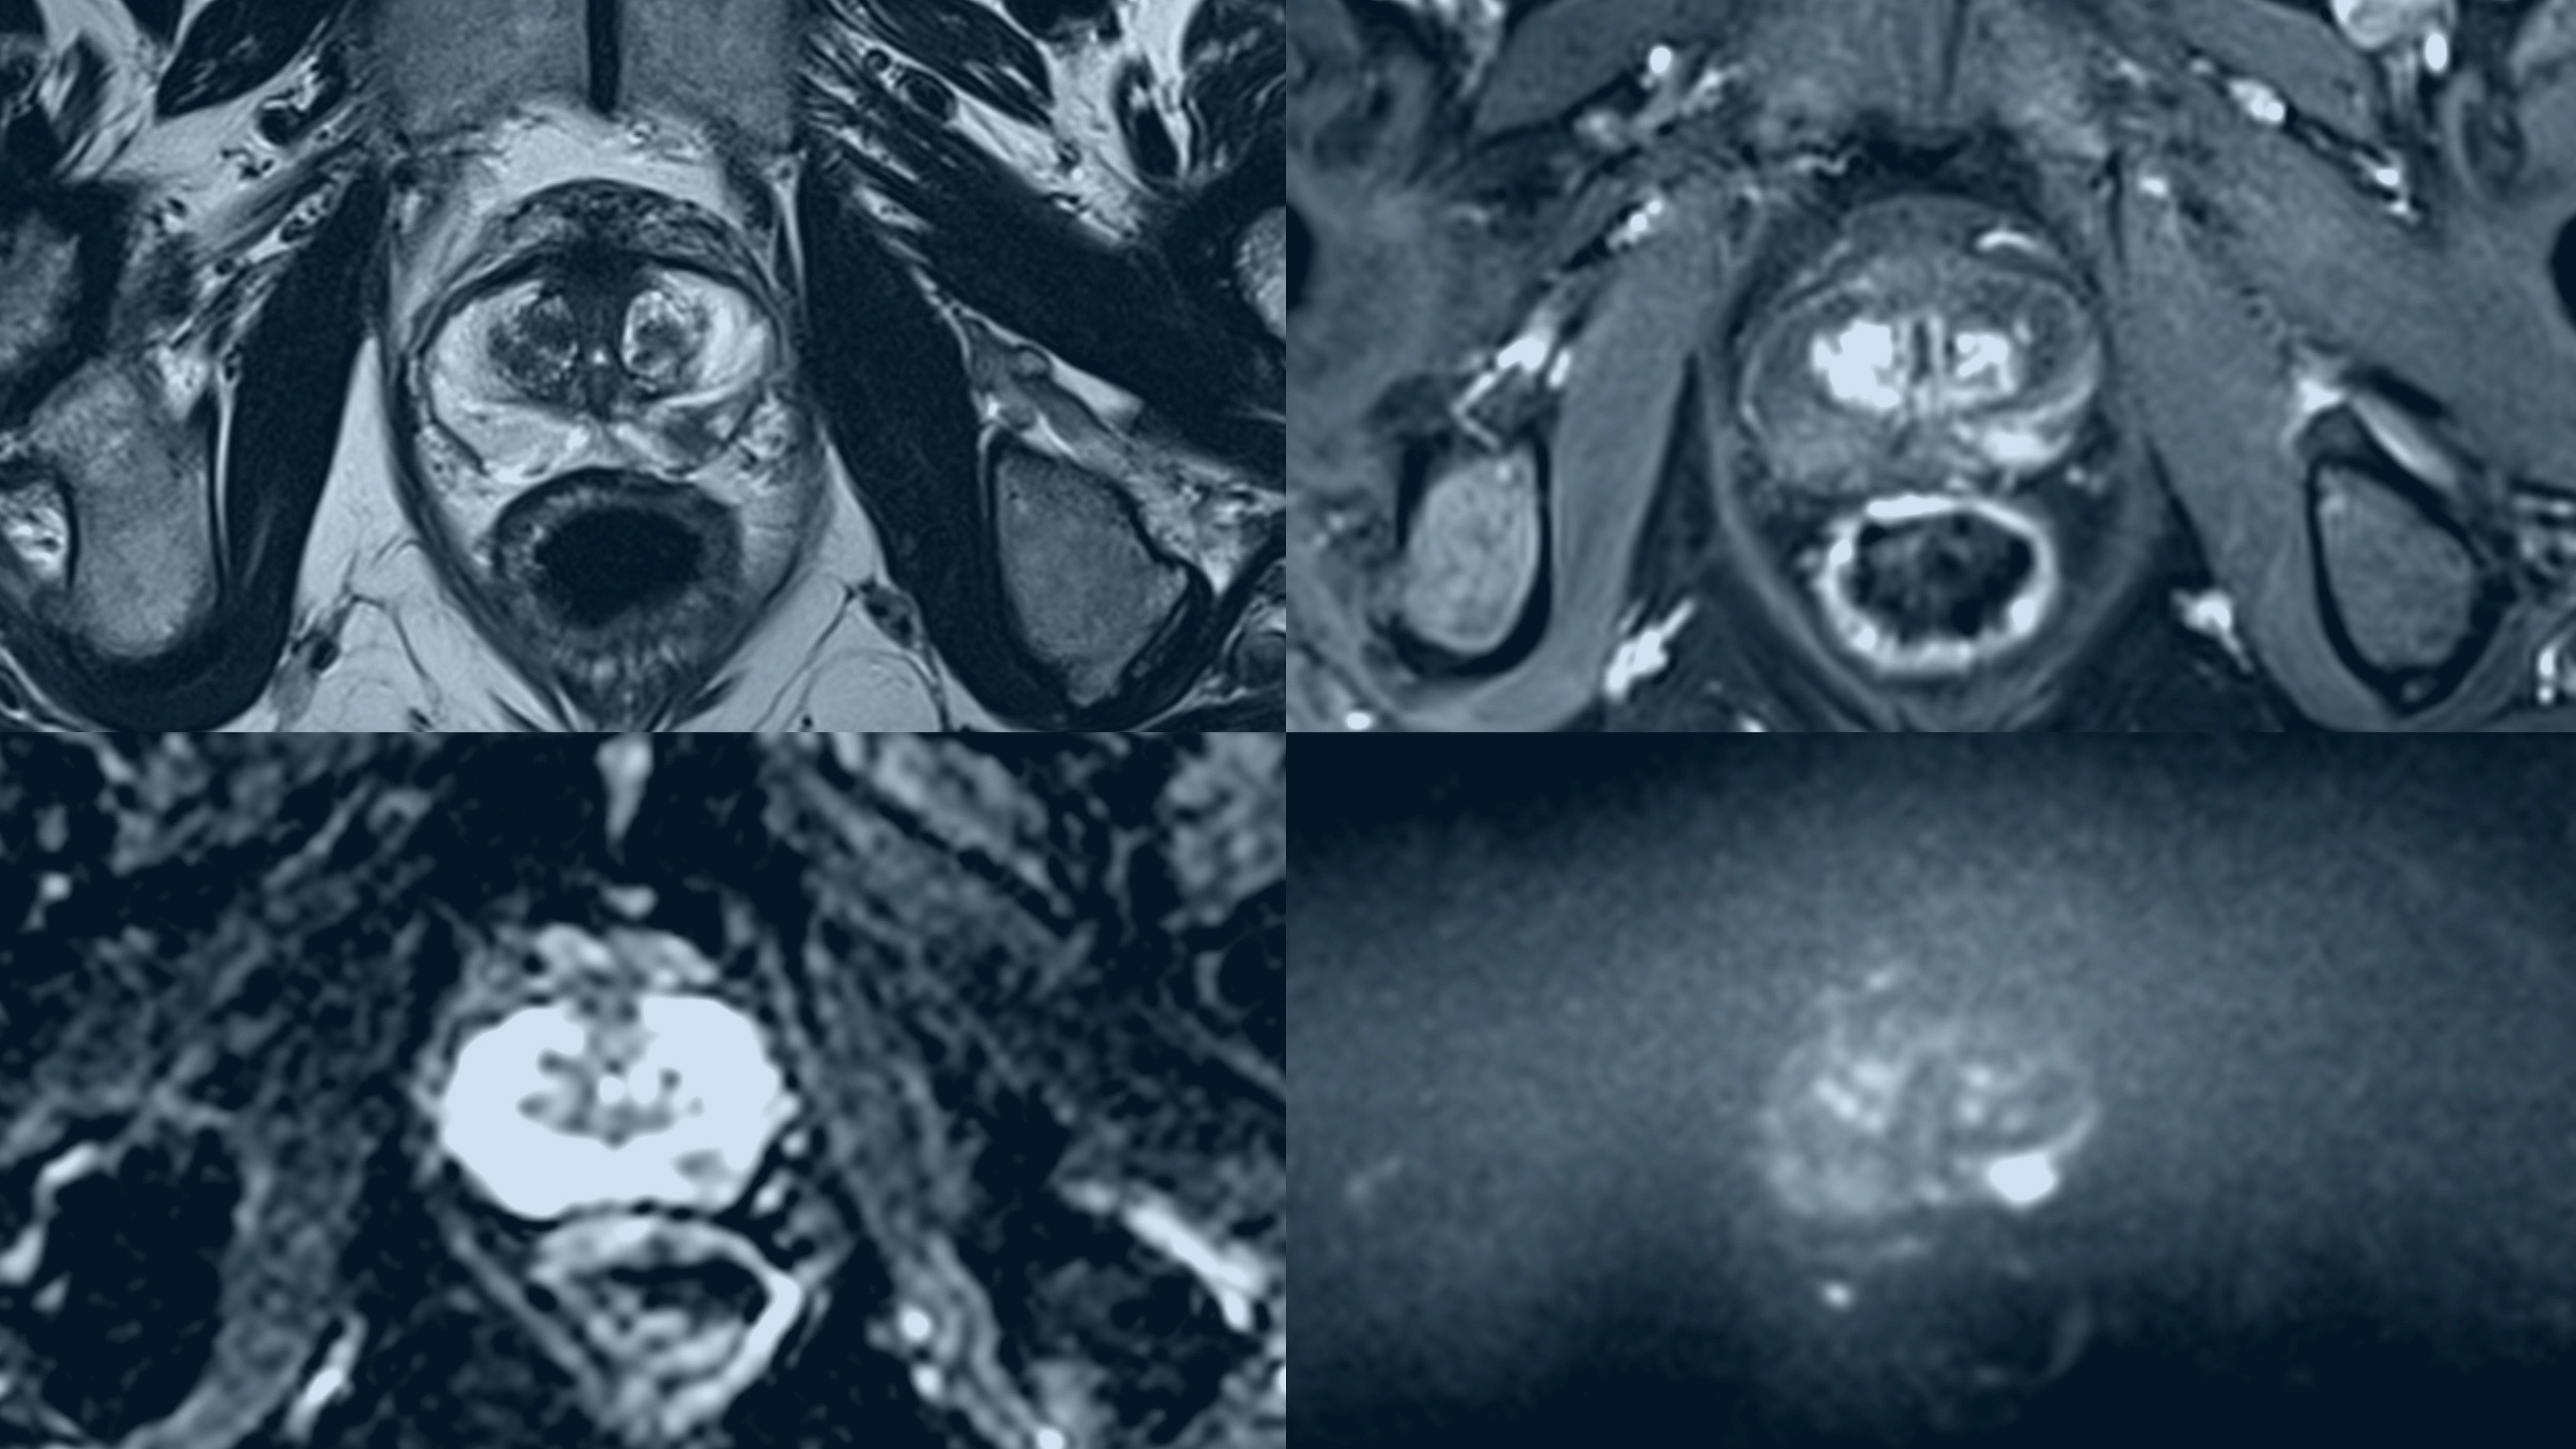

Prostate scan